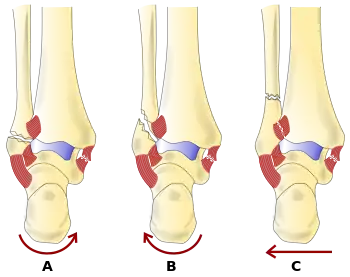

The Danis–Weber classification (often known just as the Weber classification) is a method of describing ankle fractures. It has three categories:[1]

- Type A

Fracture of the lateral malleolus distal to the syndesmosis (the connection between the distal ends of the tibia and fibula). Typical features:

- Type B

Fracture of the fibula at the level of the syndesmosis. Typical features:

- Type C

Fracture of the fibula proximal to the syndesmosis. Typical features: